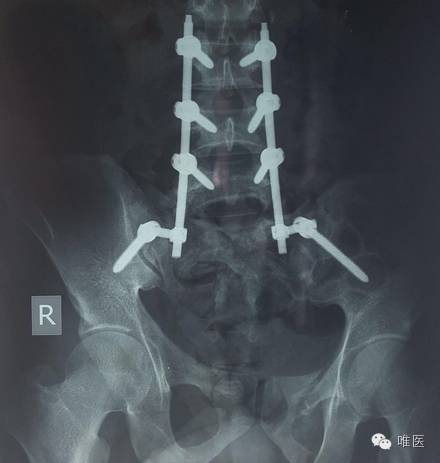

▼ 术后照片

脊柱-骨盆稳定技术(或称腰-髂固定等等)对低位骶骨横行骨折是没有复位和固定作用的。像你 这例 横行骨折且前后移位那么多,应该处理。我的经验是按脊柱骨折处理,复位后加用后路钢板固定。